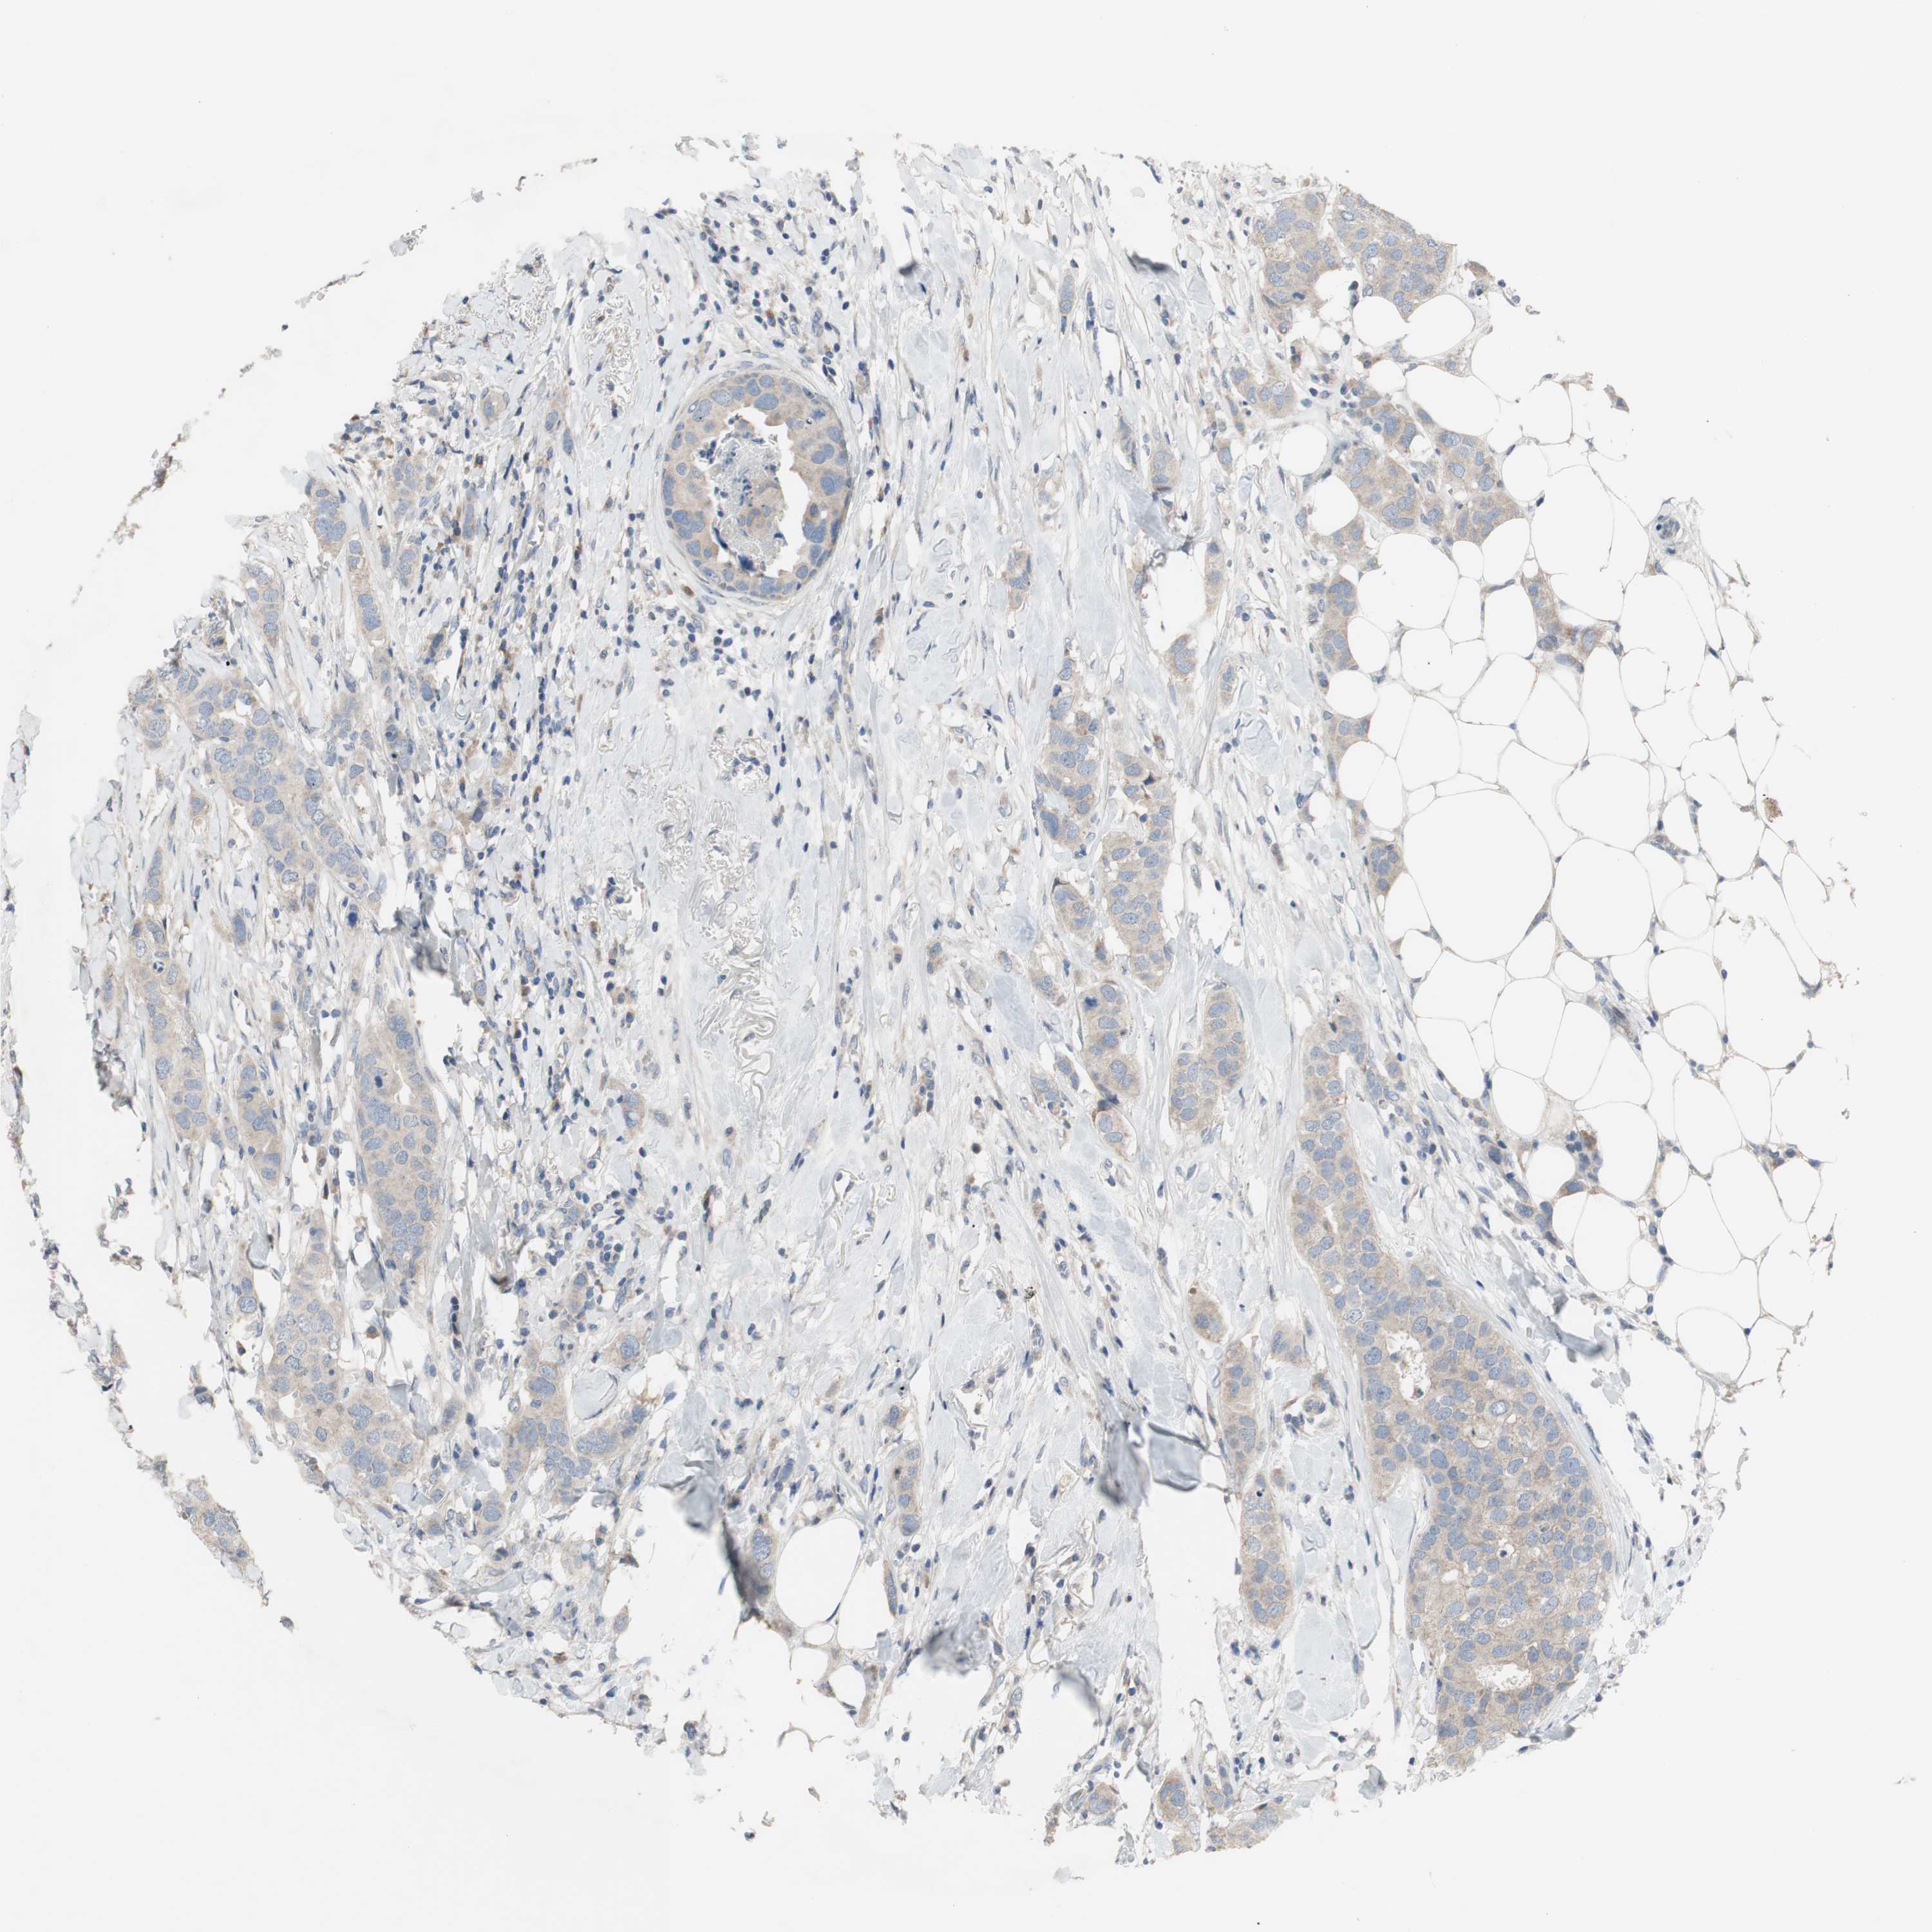

CANCER BREAST CANCER Show tissue menu

BRCA TCGA BRCA VALIDATION PROTEIN EXPRESSION